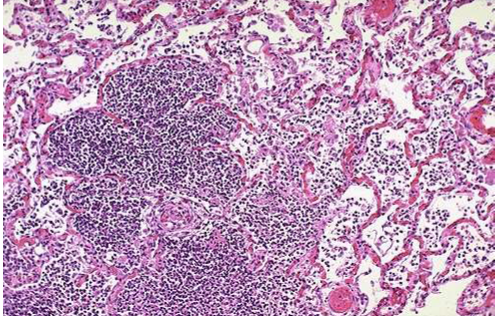

מה הממצא בתמונות הנ"ל

שחפת גרנולומות עם מרק ורוד נמקי צביעת זיל נילסן בתמונה תחתונה ימין- הורודים אלו החיידקים

מהו ככל הנראה הממצא שבתמונות

גרנולומות בריאה בעקבות שחפת